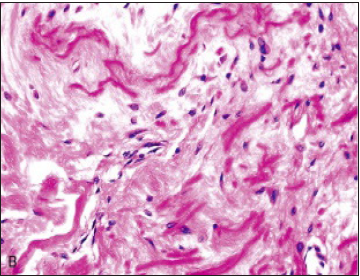

Diverse environmental and genetic theories are posited for engenderment of elastofibroma. Although disease pathogenesis is obscure, it is considered to be multifactorial. Elastofibroma is not a true neoplastic process and may be engendered by repetitive micro-trauma or friction of the inferior pole of the scapula with the thoracic wall. Repetitive, mechanical trauma induces reactive hyper-proliferation and degeneration of fibro-elastic tissue [3,4]. Elastofibroma arises in regions of limited mechanical friction and can appear within dominant and non-dominant sides. Elderly individuals commonly demonstrate an elastofibroma, the frequency of which is enhanced amongst manual workers and the right side [4]. Micro-trauma or mechanical theory is not comprehensively applicable and inadequately hypothesizes incurrence of elastofibroma (Figure 2). Vascular insufficiency may engender degenerative alterations and elastofibroma originates as a gradual neoplastic process [4]. Monoclonal proliferation with genomic instability is also incriminated in the emergence of elastofibroma. Alternatively, hereditary enzyme defects may induce reactive hyper-proliferation of fibro-elastic tissue [2,4]. Genetic predisposition with familial neoplasms can possibly denominate certain instances as a cogent family history is documented in nearly 33% of elastofibromas [2,4]. Thus, it can be summarized that elastofibroma demonstrates a multifactorial aetiology and a singular theory of disease emergence is insufficient.

Figure 2:Elastofibroma depicting bands of elastic fibres, mature adipose tissue, collagenous tissue and mature skeletal muscle.